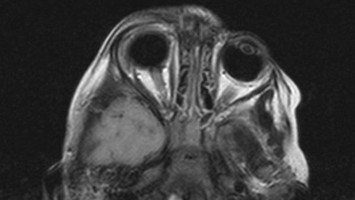

Hölzerner Fremdkörper in der Orbita? Zuerst eine CT!

Bildnachweise